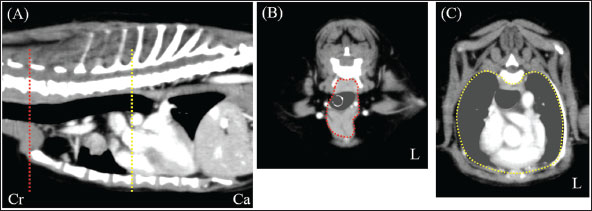

A neutered 9-year-old male Papillon weighing 3.5 kg was referred to the Okayama University of Science Veterinary Medical Teaching Hospital for examination and treatment of an incidentally discovered mass in the cranial intrathoracic cavity during regular medical checkups. The dog had no clinical signs and was in good general condition. However, a mass in the cranial thoracic region was detected by chest radiography. Blood tests showed no hypercalcemia, and arterial blood gas analysis showed no problems (Table 1). Polycythemia, slight hypernatremia, and hyperchloremia, which may be related to dehydration, were also observed. A chest X-ray revealed a mass of approximately 20 mm in the cranial intrathoracic cavity and mild expansion of the mediastinum (Fig. 1). The tumor-associated syndromes, such as megaesophagus and myasthenia gravis, were not observed. Computed tomography (CT) was performed under general anesthesia (Aquilion Lightning; Canon Medical Systems Co., Tokyo, Japan). Iopamidol (Oypalomin 300, Fuji Pharma, Japan) was used as a contrast medium (injection volume, 2.5 ml/kg [750 mgI/kg]; injection time, 15 seconds). Precontrast, arterial phase, venous phase, and equilibrium phase scans were obtained. The cranial intrathoracic mass (length, width, and height of 18.3, 16.0, and 18.6 mm, respectively) was a solitary lesion within the cranial mediastinum (Fig. 2). The mass was well demarcated, and there was no evidence of invasion into the surrounding blood vessels. The CT values of the mass were 43.2, 50.6, 113.1, and 102.2 HU for the precontrast, arterial, venous, and equilibrium phases, respectively (Fig. 2). These contrast enhancement effects were a preliminary diagnosis that the mass was a thymoma (Von Stade et al., 2019). Enlarged surrounding lymph nodes or distant metastasis were not detected. Due to the small size of the mass and its absence from the thoracic cavity margin, preoperative pathological examination could not be performed. Based on the CT results, the mass was provisionally diagnosed as a thymoma. The thymoma volume was measured from the length, width, and height by computed tomography using the elliptical volume formula. The cranial intrathoracic volume was measured using a 3D image analysis software (Ahmics-VAZE, PetCommunications Co., Ltd., Osaka, Japan). The cranial intrathoracic region between the first and fourth sternum at the beginning of the cranial intrathoracic cavity was assumed to be the surgical space for VATS-T (Fig. 3). The dorsal cephalic end was designated as the point where the first sternum extends perpendicularly and joins the thoracic vertebrae, and the dorsal caudal end was designated as the point where the fourth sternum extends perpendicularly and joins the thoracic vertebrae. This region was extracted and its volume was measured using the 3D volume rendering function by Ahmics-VAZE. The ratio of thymoma volume to cranial intrathoracic volume (T/CI ratio) was calculated as follows: thymoma volume/cranial intrathoracic volume × 100). The thymoma volume was 2.3 cm3, the cranial intrathoracic volume was 97.7 cm3, and the T/CI ratio was 2.4%. The thymoma volume was calculated using the approach in a previous report of two cases that described the thoracoscopic resection of thymomas (Mayhew and Friedberg, 2008). We also calculated the cranial intrathoracic volume for the dog, as it was of the same breed and weight as the two reported cases. Subsequently, we calculated the T/CI ratio. In previous reports, the thymoma volumes were 9.5 cm3 and 36.6 cm3, respectively, and the cranial intrathoracic volume was 892.8 cm3. The T/CI ratios were 1.1% and 4.1%, respectively.

Fig. 3. CT imaging of the cranial intrathoracic cavity. (A) Sagittal section. (B) Transverse section of the first sternum. (C) Transverse section of the fourth sternum. The surgical space for VATS was assumed to be the cranial intrathoracic cavity between the first and fourth sternum (A; red and yellow dotted line, respectively). Cross-sections (B and C) of the two dotted lines. The circular areas enclosed by dotted lines within the cross-sections were continuously extracted and designated as the intracranial thoracic cavity, and their volumes were measured. (L): Left side, (Cr): Cranial, (Ca): Caudal.